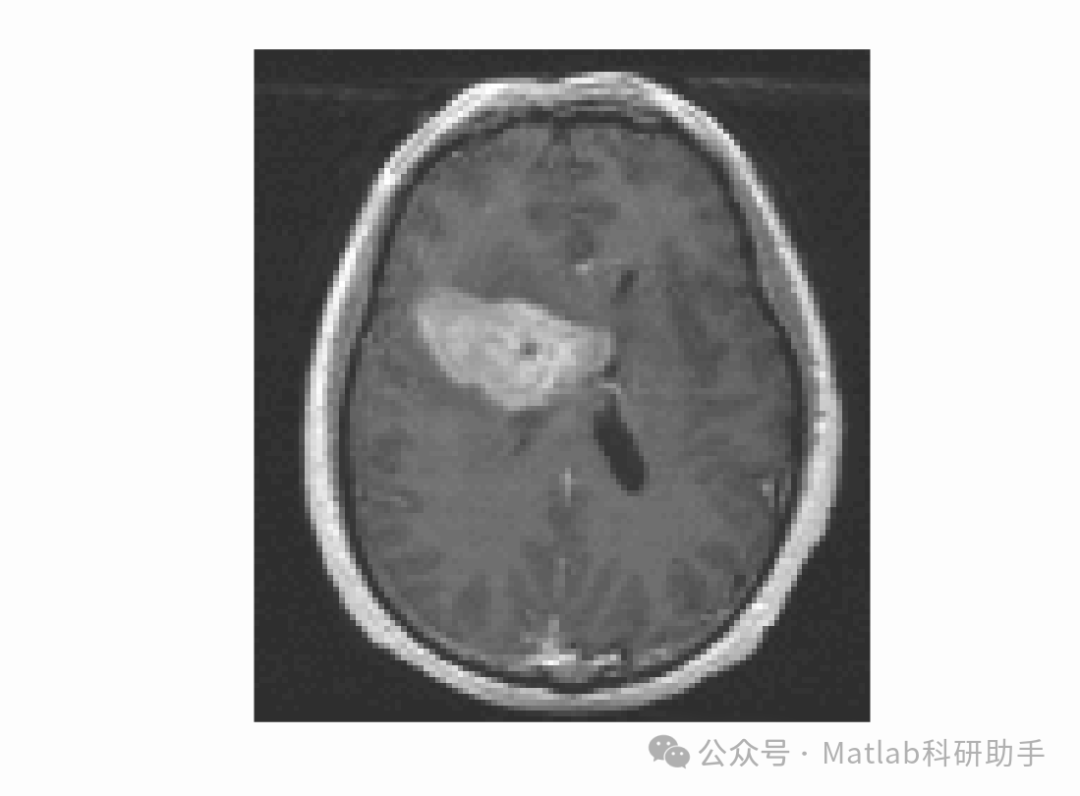

图像分割是计算机视觉领域中的一个核心任务,旨在将图像划分为不同的区域或对象,以便于后续的分析和理解。在众多图像分割方法中,主动轮廓模型(Active Contour Models, ACMs)以其能够有效处理图像噪声和弱边缘等复杂情况而受到广泛关注。传统的几何活动轮廓模型,如Chan-Vese模型,主要依赖于图像的全局信息,通过最小化能量泛函来驱动轮廓演化。然而,面对具有复杂纹理、灰度不均匀或局部特征显著的图像时,全局模型往往表现出局限性。为了克服这些限制,研究者们提出了基于局部信息的主动轮廓模型。其中,由局部高斯分布拟合能量驱动的活动轮廓模型,采用变分水平集形式,为处理此类复杂图像分割任务提供了有效途径。

相较于传统的全局模型,局部高斯分布拟合能量驱动的活动轮廓模型展现出显著的优势。首先,它能够有效处理灰度不均匀的图像。在许多医学图像或自然图像中,目标对象内部的灰度值可能不是均匀的,而局部模型通过考虑每个局部区域的独特统计特性,能够更好地适应这种变化。其次,该模型对噪声具有更强的鲁棒性。通过局部区域的统计平均,模型能够抑制随机噪声对分割结果的影响。第三,它在处理弱边缘或模糊边缘时表现更优。局部信息的使用使得模型能够更好地捕捉那些在全局尺度上不明显的边缘特征。

由局部高斯分布拟合能量驱动的活动轮廓模型,采用变分水平集形式,在图像分割领域具有重要的理论意义和应用价值。它通过充分利用图像的局部统计特性,有效克服了传统全局模型在处理复杂图像时的局限性。尽管仍面临一些挑战,但随着算法的不断优化和计算能力的提升,这类模型有望在医学图像分析、遥感图像处理和目标识别等领域发挥更大的作用,为实现更精确、更鲁棒的图像分割提供强有力的工具。未来的研究方向可以包括探索更先进的局部统计模型、结合深度学习方法以及开发更高效的优化算法,以进一步提升模型的性能和适用范围。